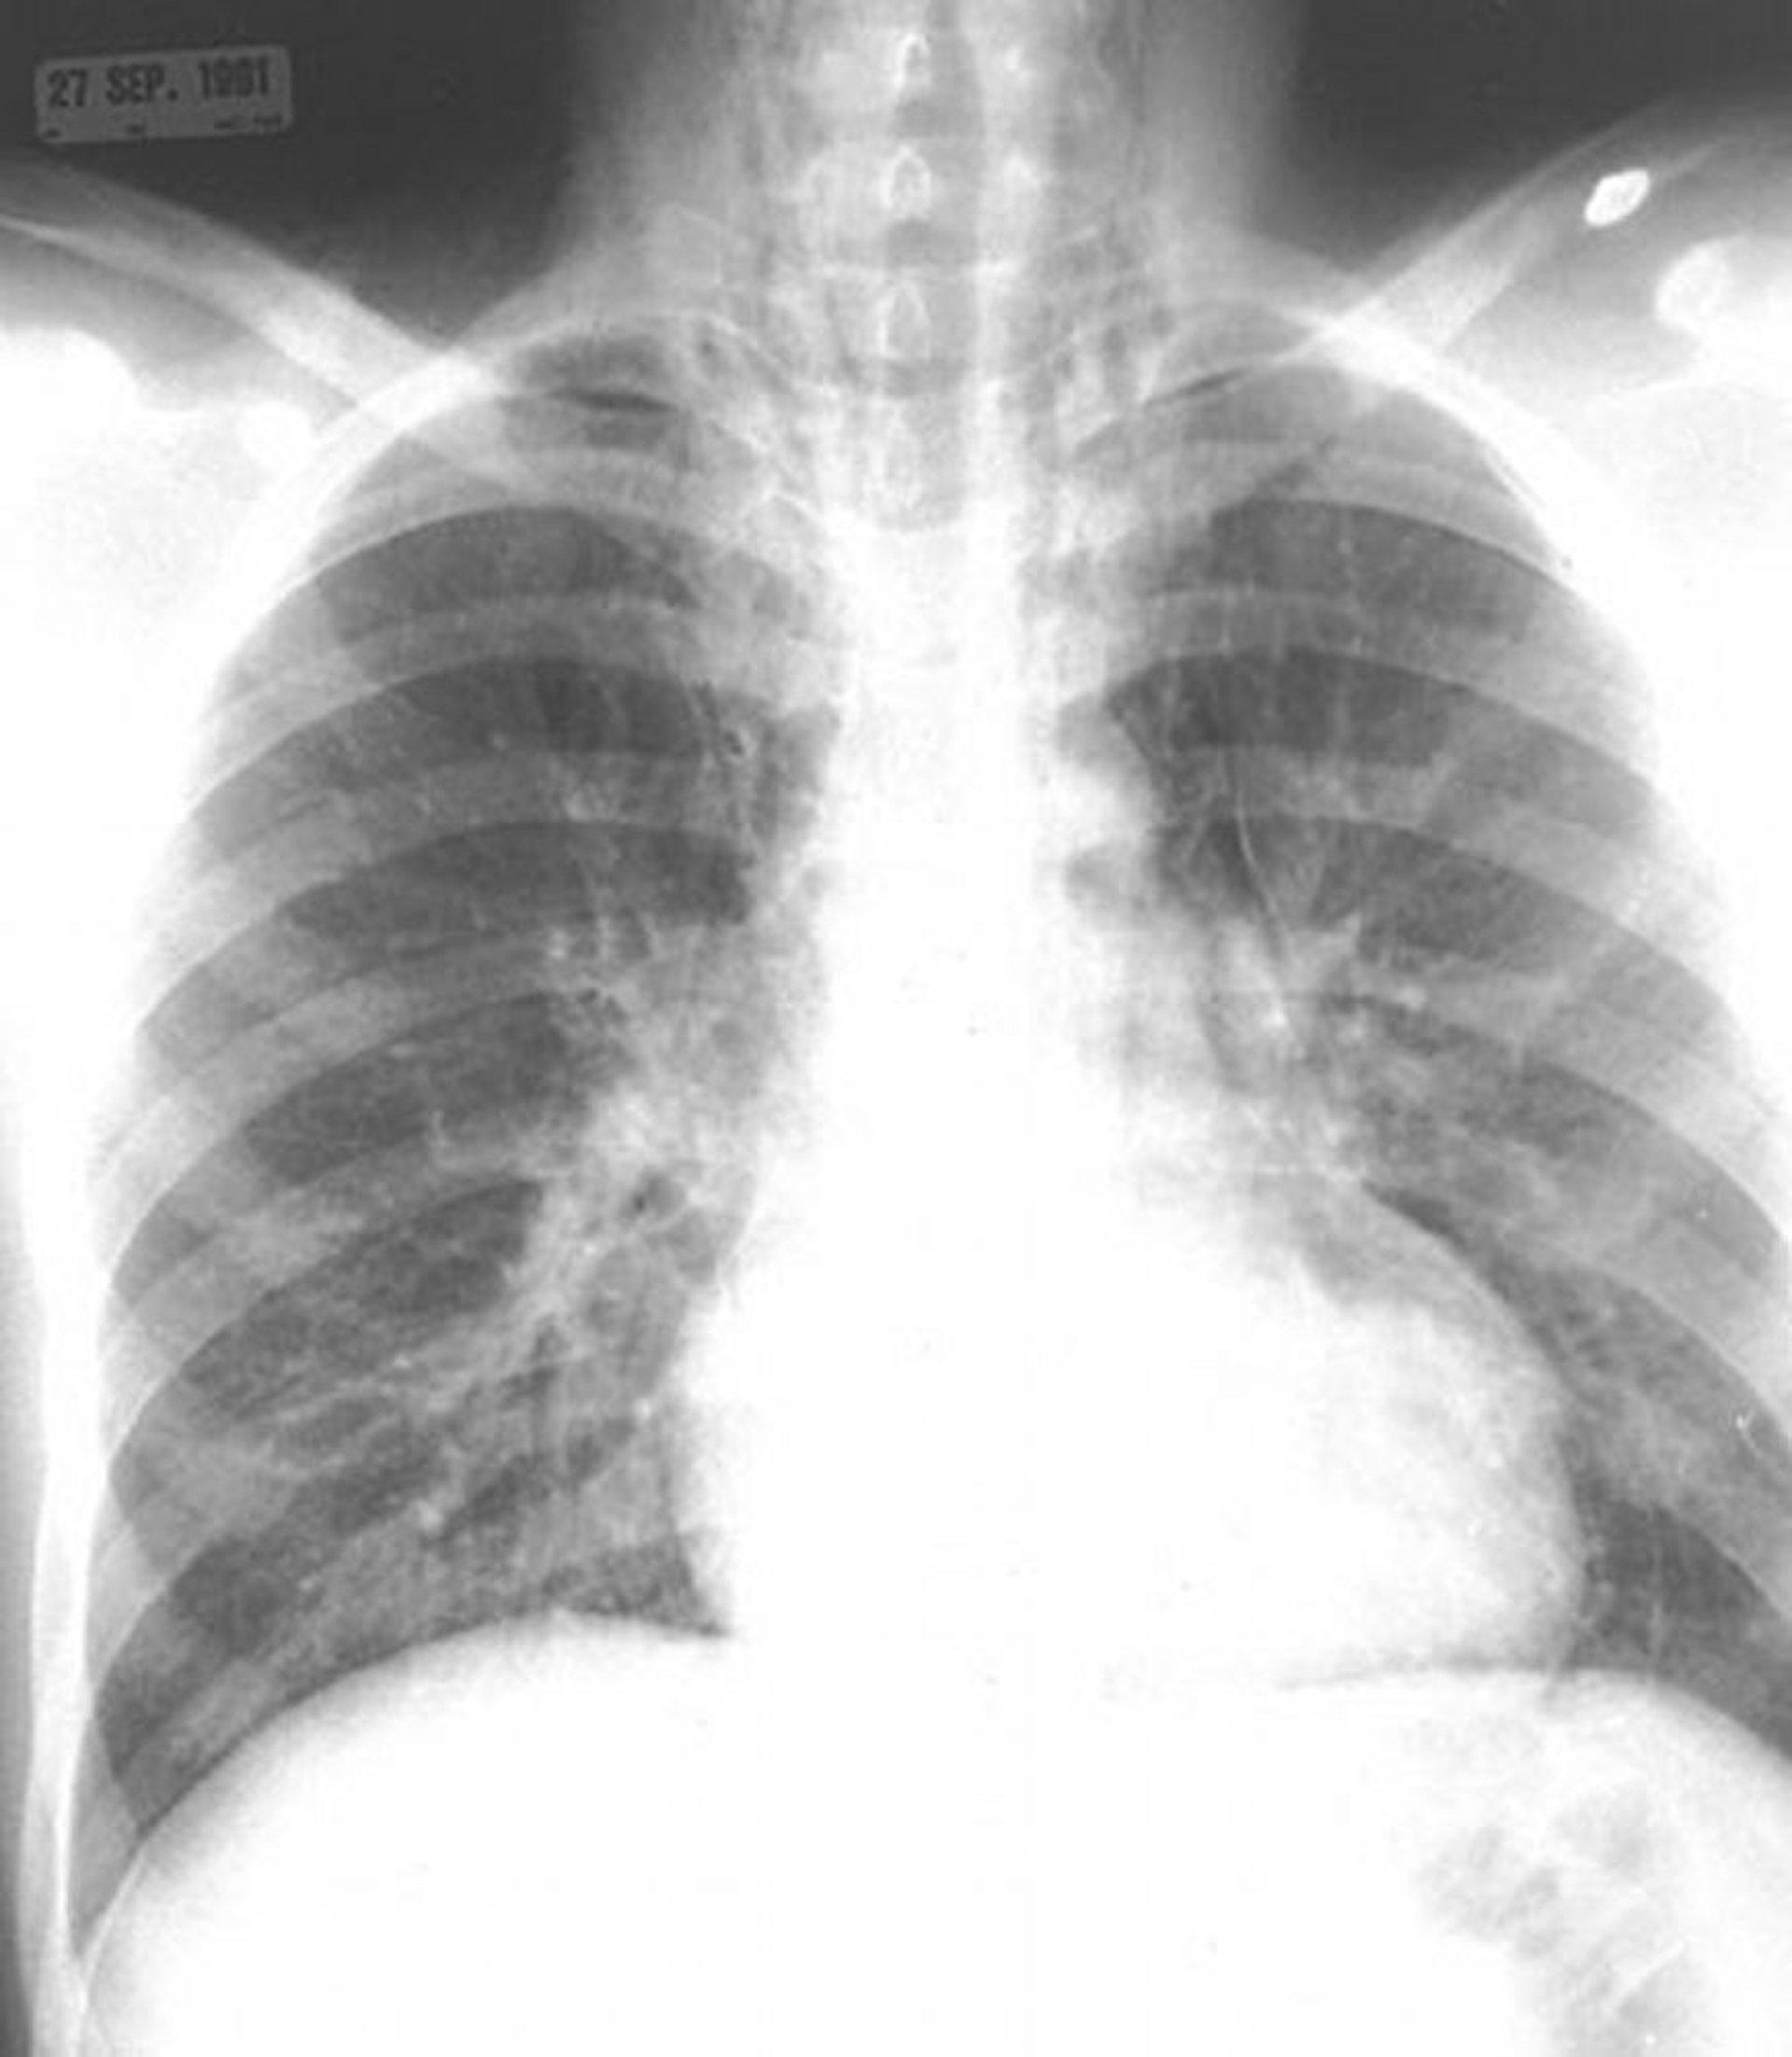

Pneumomediastino

Notare l'aria nel mediastino e nei tessuti molli del collo.